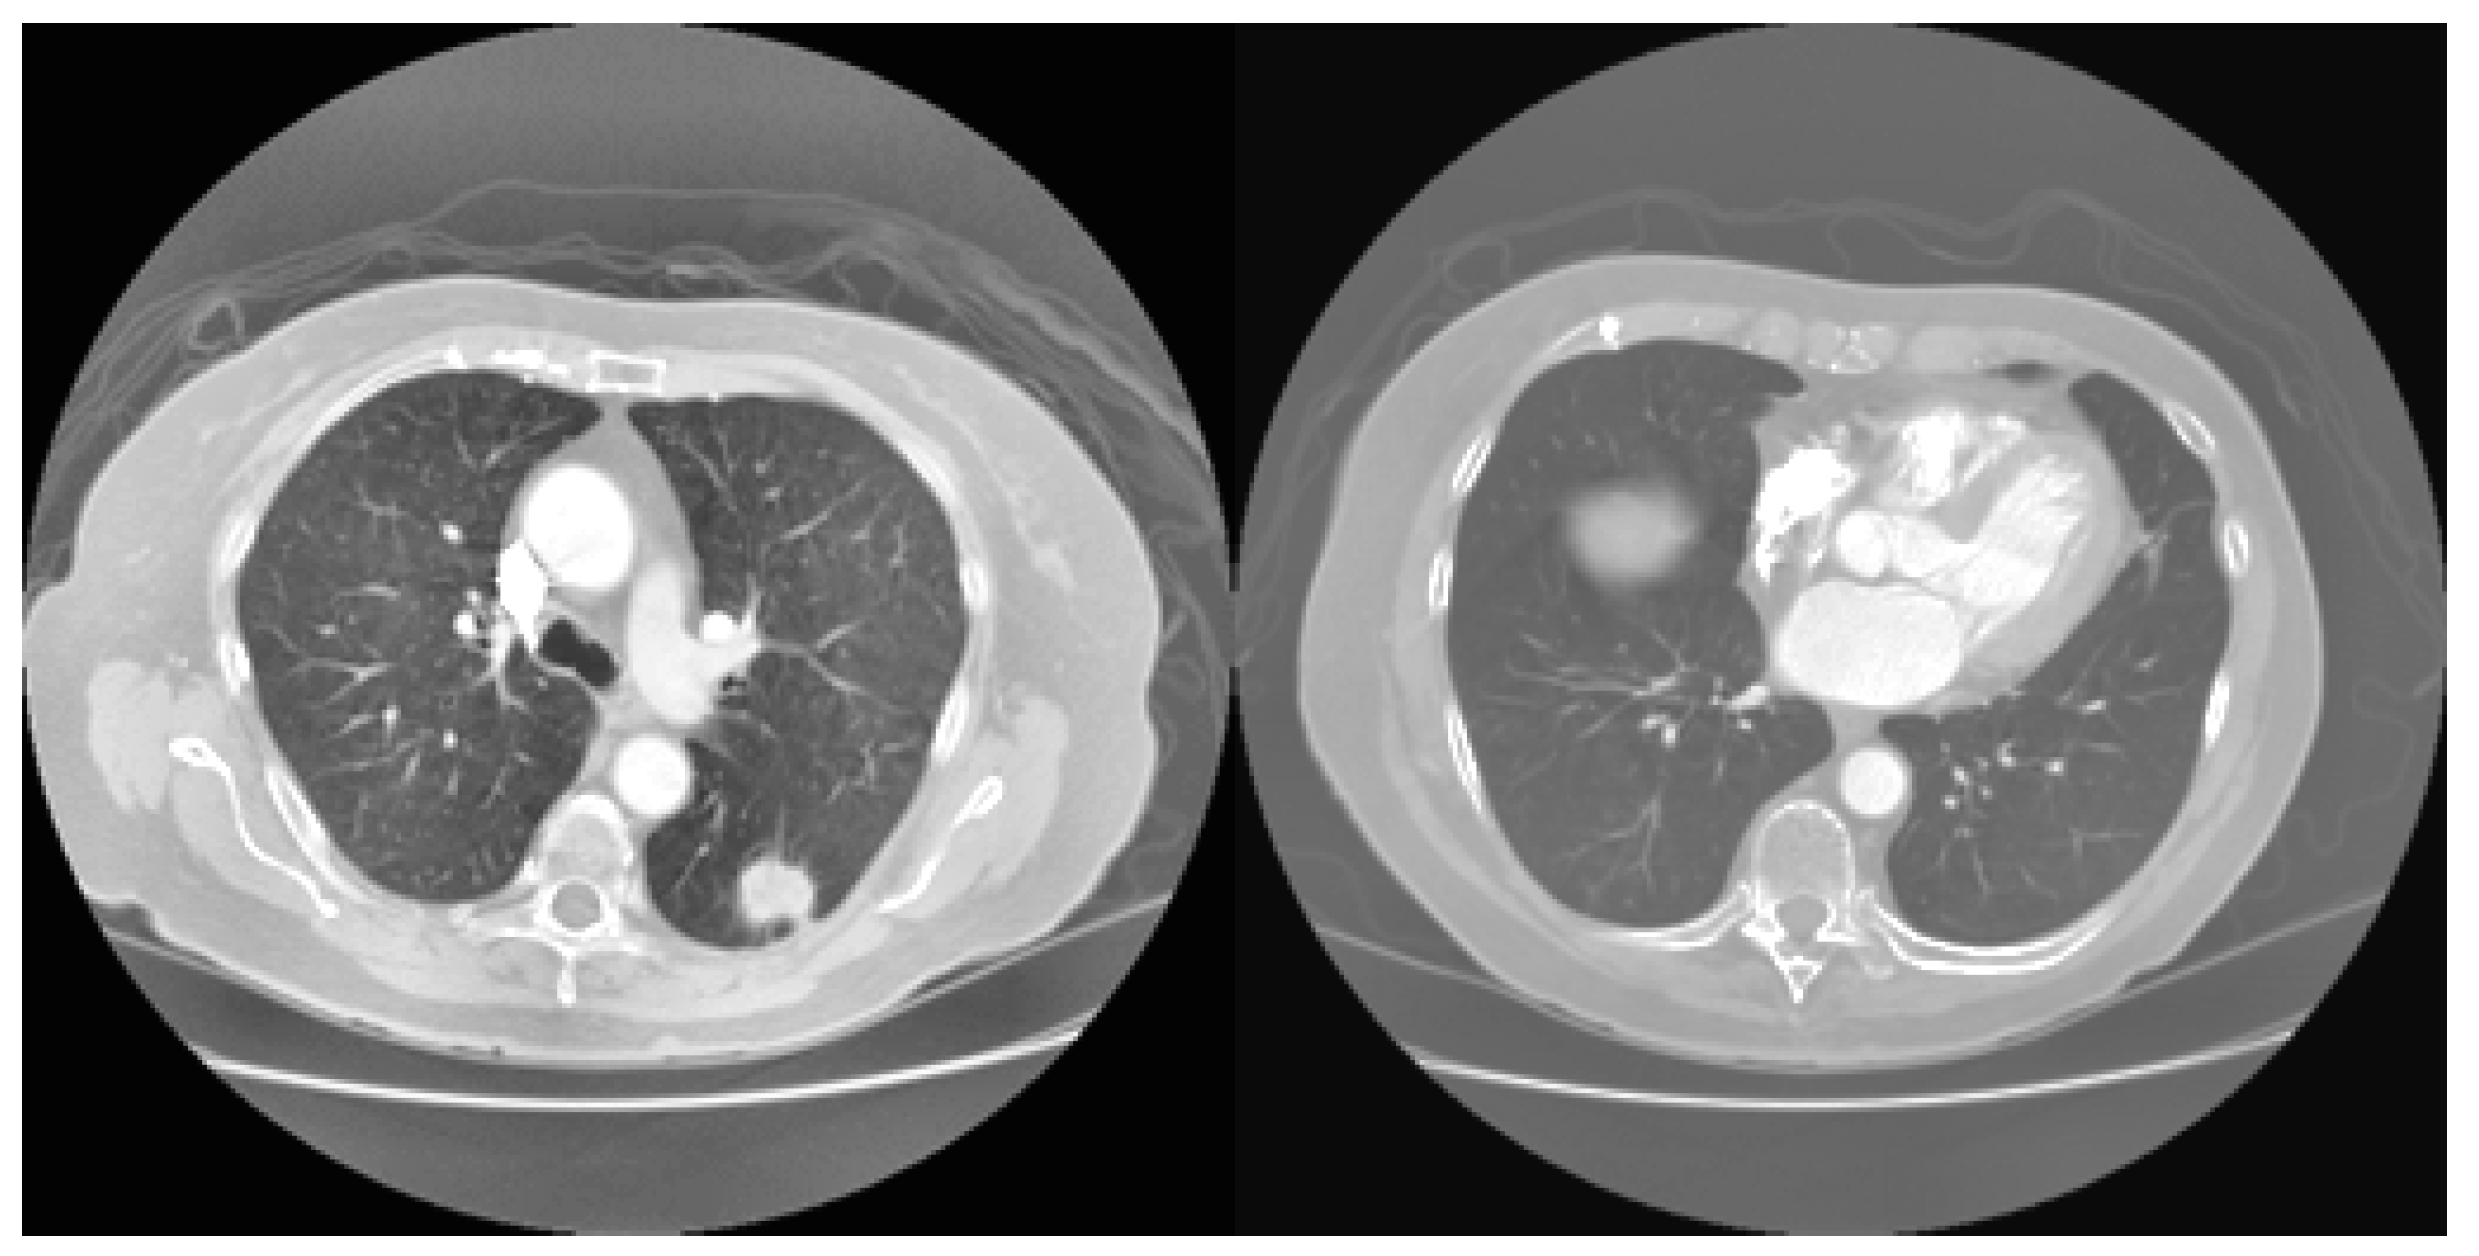

3.1. Automatic Lung Parenchyma Mining and Border Restoration (ALPM & BR)

3.1.1. Automatic Single-Seeded Region Growth (ASSRG) Algorithm

3.1.2. Novel Hybrid Border Concavity Closing (NHBCC) Algorithm